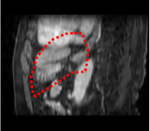

An example of CT/CBCT and MR/CBCT registration results are shown in figures 3 and 4, respectively. For both cases, the CBCT image (first column) was acquired intra-operatively after needle insertions and was employed as a reference for image registration. The pre-operative image is displayed before registration (second column), after PM-EA (third column) and after PM-EA+Evo (fourth column). The occurrence of patch shifts is reported for each spatial direction in panels (m–o): for each histogram, the shift with maximal occurrence is shown by the red dashed line. For panels (a–l), a ROI — manually defined on the CBCT image/encompassing the liver — is shown using red dash lines. Our visualization shows an improved correspondence of the contour of the liver with the manually defined liver boundary when the PM-EA solution is employed (see 3(c,g,k) and 4(c,g,k)). Moreover, an even better correspondence of the contour is observable using the PM-EA+Evo solution (see 3(d,h,l) and 4(d,h,l)).

Trans.

[X-Y]

CBCT

(a)

MRI / No registration

(b)

MRI / PM-EA

(c)

MRI / PM-EA+Evo

(d)

Sag.

[X-Z]

(e)

(f)

(g)

(h)

Cor.

[Y-Z]

(i)

(j)

(k)

(l)

(m)

(n)

(o)